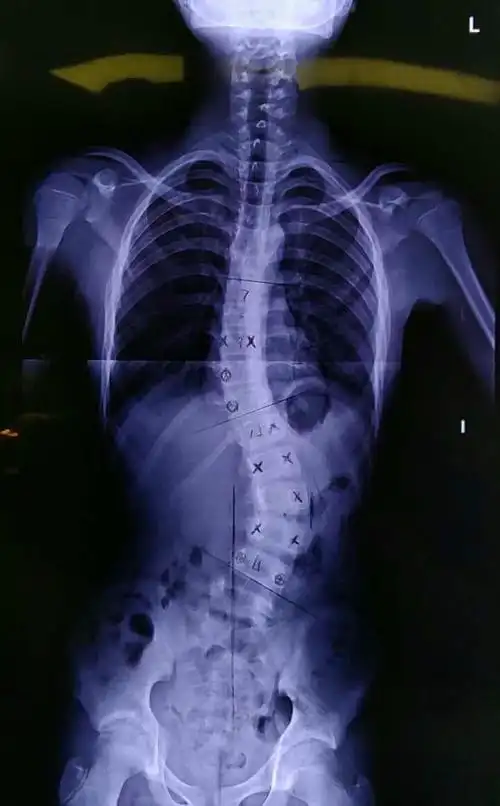

脊柱侧弯手术,患者应该怎样进行康复训练(脊柱侧弯手术后如何进行康复

最近完成的一例特发性脊柱侧弯

【医文医话】特发性青少年脊柱侧弯的多学科综合治疗模式(二)

特发性脊柱侧弯的运动训练原则 (原创)

近年来,青少年脊柱侧弯的现象越来越普遍,一般没有明显的临床表现,等